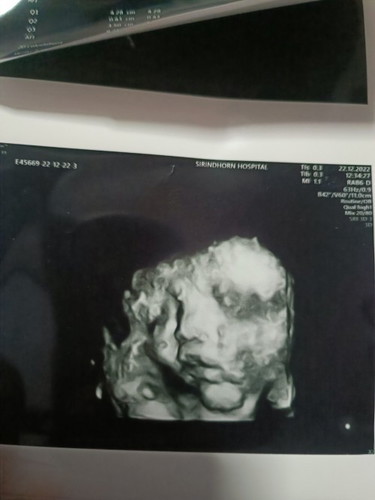

ตอนนี้36วีคอยากรู้ว่าน้องหนัก2400ตัวเล็กไปไหมคะ?

ตอนนี้36วีคอยากรู้ว่าหนัก2400นี่ตัวเล็กไปไหมคะหรือกำลังพอดีคะ ทีม มกราคะ💝 ลูกๆของแม่หนักเท่าไหร่กันบ้างคะ☺️☺️ #ท้องแรกคะ

อ่านเพิ่มเติมกำหนด12มค66คะ แต่นัดผ่า2มค66 ตื่นเต้นมากคะ ใกล้แล้ว น้ำหนักลูกตอนที่ไปหาคุณหมอมาวันที่21/12ลูกหนัก2750 พอวันที่ห่างกัน4วันคะ 25/12ไปหาหาหมอ น้ำหนักลูก 3200 คะ วันคลอดรอลุ้นอีกทีคะว่า จะหนักเท่าไร